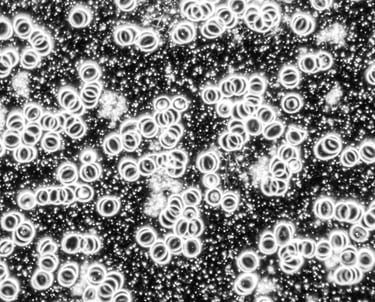

1. Levend Bloed Analyse

Analyseer uw gezondheid met onze unieke donkerveld microscooptechniek voor diepgaand inzicht